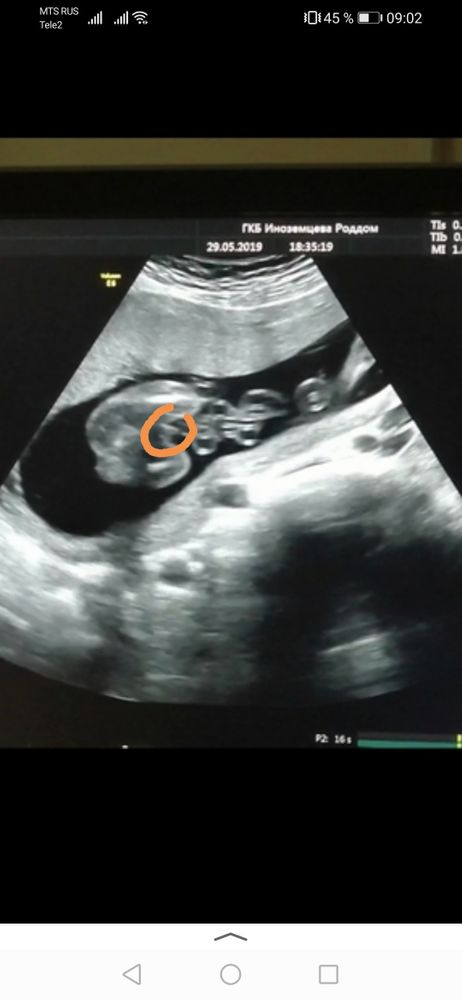

Анастасия, наоборот, на этом сроке всё отчётливо и видно. Органы сформированы и дальше просто растут пропорционально. Вот Вам мой для сравнения в 19 недель. Изображение

06.07.2022